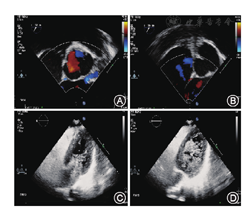

46例中患者中,A组17例,13例(13/17)右心声学造影无右向左分流(图1),4例(4/17)1级分流。B组20例,100%发生右向左分流,其中5例(5/20)1级分流,15例(15/20)2~3级分流(图2)。C组9例,100%发生右向左分流,其中2例(2/9)1级分流,7例(7/9)2~3级分流(图3)。

对于彩色多普勒微弱左向右分流和双向分流患者,表明其左心房和右心房压力相差不大,研究中患者分为两种情况,一种(B组6例,C组4例)通过三尖瓣返流估测肺动脉收缩压,提示存在轻度肺动脉高压(35~50 mmHg);其余(B组14例,C组5例)心脏正常,未见三尖瓣反流及肺动脉高压表现。两组患者右心声学造影全部出现右向左分流,大部分(15/20及7/9)为2~3级分流,说明此两组患者在各种原因导致右心房压力短暂性(如咳嗽、打喷嚏、valsalva动作等)或持续性(肺动脉高压)增高的情况下,右心系统的栓子完全有可能进入左心系统,从而引起矛盾性栓塞。B组与C组隐源性卒中发病率明显增高,也证实了这一点。微弱左向右分流组一例患者,平静状态下,其卵圆孔缝隙为0.15 cm,在valsalva动作时可以达到0.3 cm。对于彩色多普勒明显左向右分流的患者,由于左心房压力明显高于右心房,发生反常栓塞的可能性是否会小一些,以及卵圆孔未闭相关性隐源性卒中的特异性表现,均需要进一步大样本的研究。

46例患者中,隐源性卒中18例,头颅MRI检查显示梗死病灶,其中A组3例(3/17),B组10例(10/20),C组5例(5/9),B组与C组发病率明显高于A组,差异均有统计学意义(均P<0.05)。18例隐源性卒中患者中梗死灶呈单发8例,多发10例。